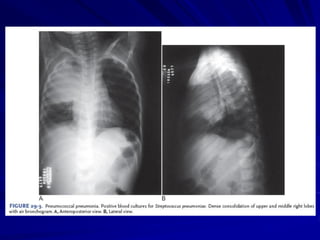

Phân loại theo bệnh cảnh lâm sàng

VP điển hình: diễn tiến cấp tính với sốt cao, rét

run, đau ngực, ho có đàm. Xquang phổi: có

hình ảnh VP thuỳ. Điển hình: VP do phế cầu.

X QUANG PHỔI

Heulitt (1988): Xquang có:

Độ nhạy cảm: 45 %

Độ đặc hiệu: 92 %

X quang: dấu hiệu chỉ điểm kém cho

nguyên nhân VP

• Không có hình ảnh Xquang đặc hiệu

cho VP do virus, TN không điển hình

• Không thể giúp phân biệt VP do VT

hay do virus

• VP thùy/Xquang: giá trị cao cho VP vi

trùng nếu kèm sốt cao (39oC), BC tăng

(>20.000/mm3) (Spec=74%)